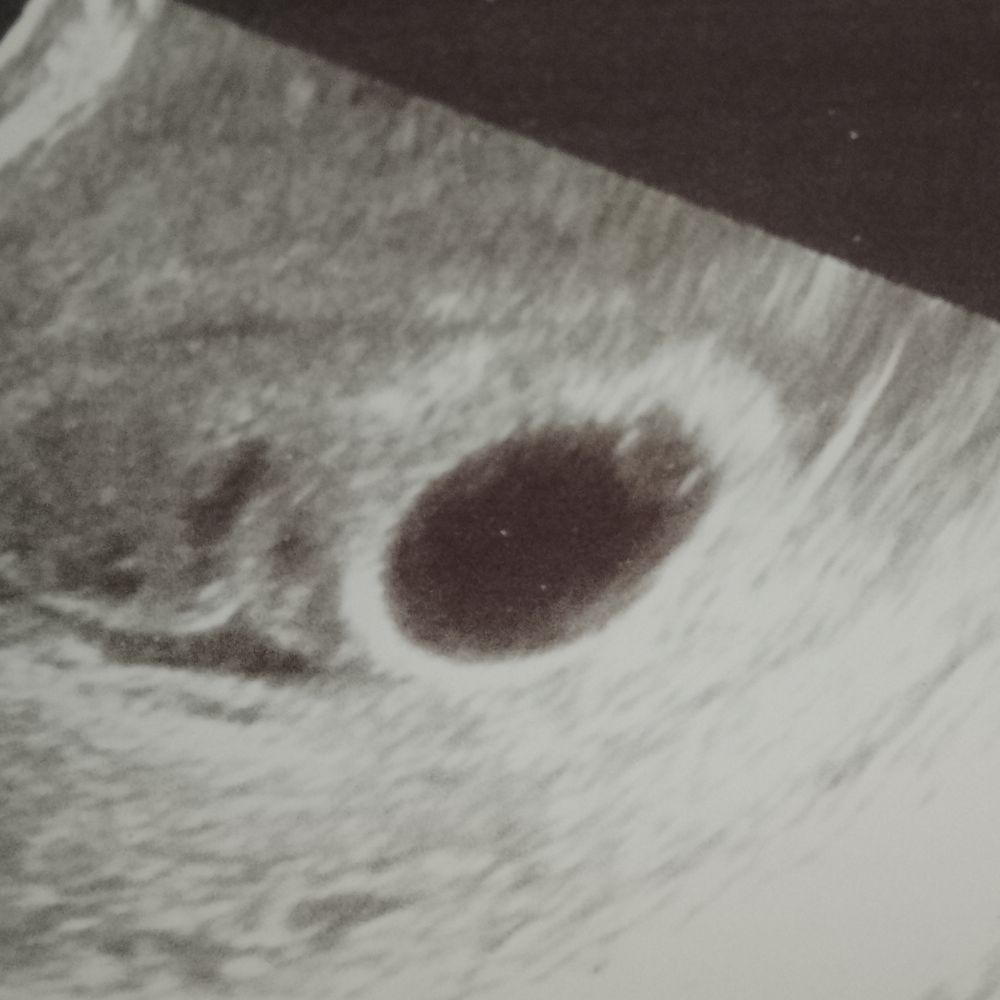

13 неделя очередное узи

Отсутствие желточного мешка и эмбриона Незначительное укорочение шм при беременности, голова ребёнка низко